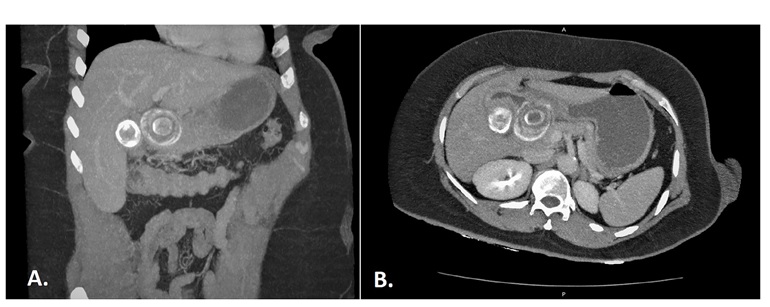

Bouveret syndrome. A 59-year-old woman, she consulted the emergency for generalized abdominal pain, accompanied by nausea and vomiting of 72 hours of evolution. On physical examination, he presented a soft, distended abdomen, without signs of peritonism. The computed tomography revealed gastric obstruction secondary to the impact of a stone in the duodenal bulb. Gastrotomy was performed with extraction of lithiasis at the duodenal level and at the vesicular level, a raffia was performed with separate stitches and drainage was placed. Bouveret's syndrome, caused by a stone, lodges in the bulb and causes gastric obstruction secondary to a cholecystoduodenal or choledochododenal fistula. It occurs between 1 and 3% of all cases of gallstone ileus, most often in women aged 70 to 75 years.

Clinically it presents with epigastric pain, nausea and vomiting.